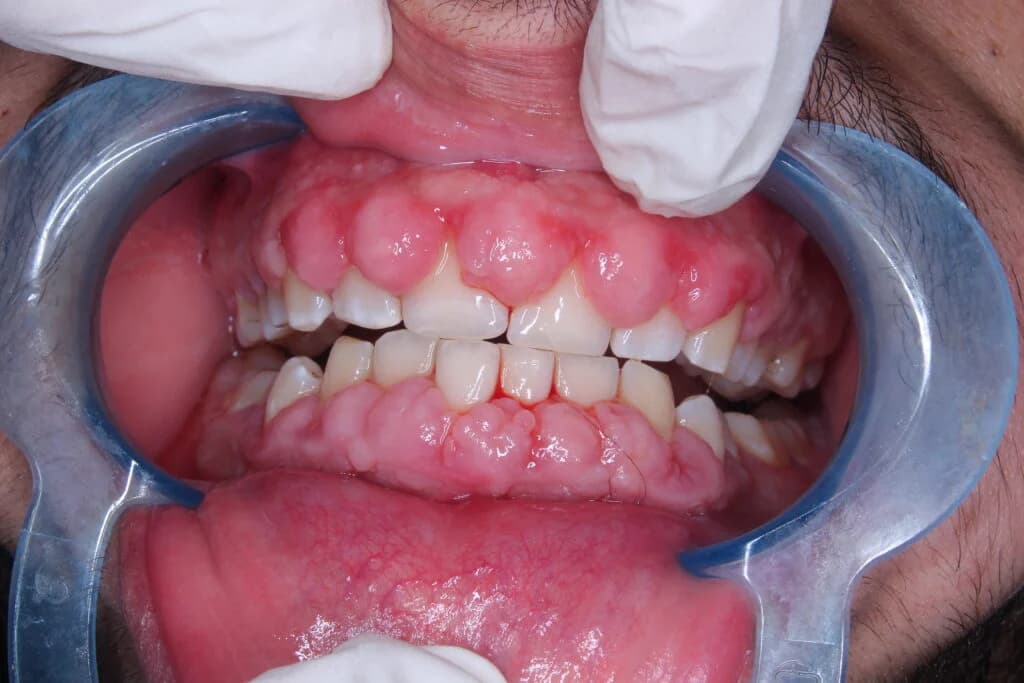

Excess Gum Tissue

Some individuals naturally have more gum tissue covering their teeth.

Gum Inflammation

Poor oral hygiene or conditions like gingivitis can cause swollen gums, making them more visible.